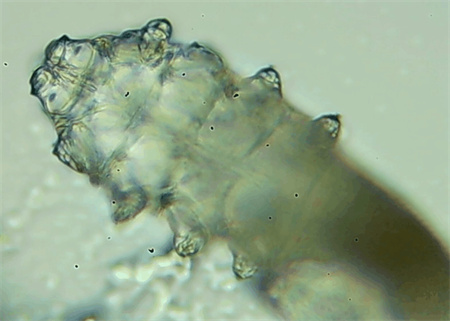

從一只眼睛的上眼瞼和下眼瞼處各拔3根睫毛,放在玻片上。

把玻片放到顯微鏡下觀察,通過電腦實時傳送的畫面,可以查看到這些拔下來的睫毛上是否有螨蟲。

這種螨蟲叫做蠕形螨,他們通常呈乳白色、半透明的細長狀,擁有四對腳。它們跟被子上的塵螨可不是同一種。